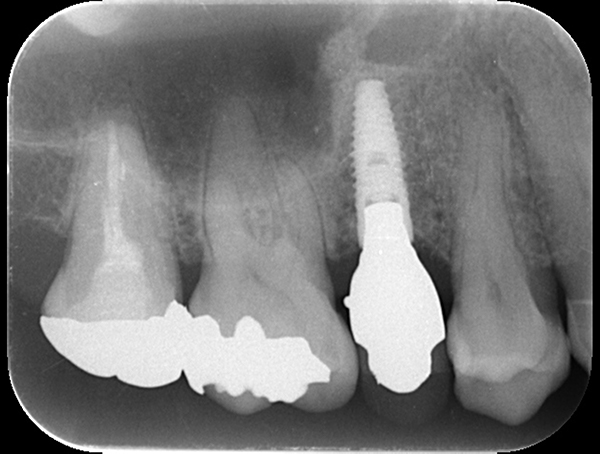

インプラントが2本入っているが左右でインプラント体の種類が異なります。

麻布十番歯科の左右で異なるインプラント体を使用したレントゲン写真

上顎では上顎洞にインプラントを入れないようにするために、ソケットリフトという骨を足す手術を行うことがあります。 当院ではこちらの手術はインプラント手術とは別に約15万円かかります。

麻布十番歯科のソケットリフト手術後のレントゲン写真